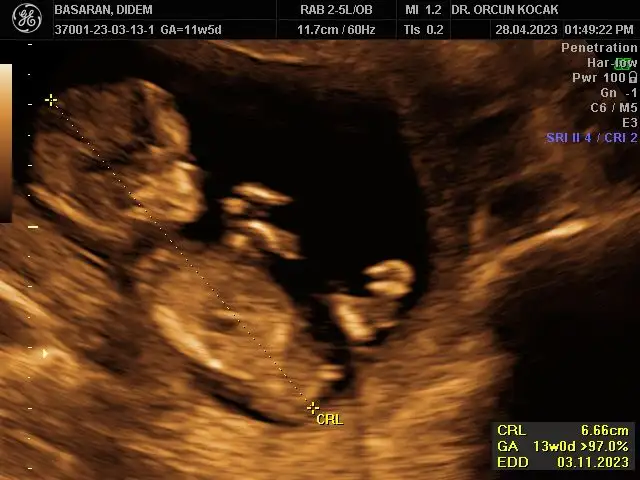

Merhabalar bende 11+5 im tahminlerinizi çok merak ediyorum kızlar sizce ne olabilirRamzi de nub’ u da erkek görünüyor canım

Bu ultrason görüntüsü mü yoksa alttan mı? Ultrasonsa benimkiyle aynı da kafatası bile. Ay ultrason yazmışsın zaten ya farketmedim. Sağlıkla kucağına al inşallah evinize neşe getirsin.Ultrason görüntüsü bugünün böyleydiben erkek hissediyordum bu sefer bulantım filan olunca ama değilmiş hiç teorilere bakmadım açıkçası o yüzden bilmiyorum